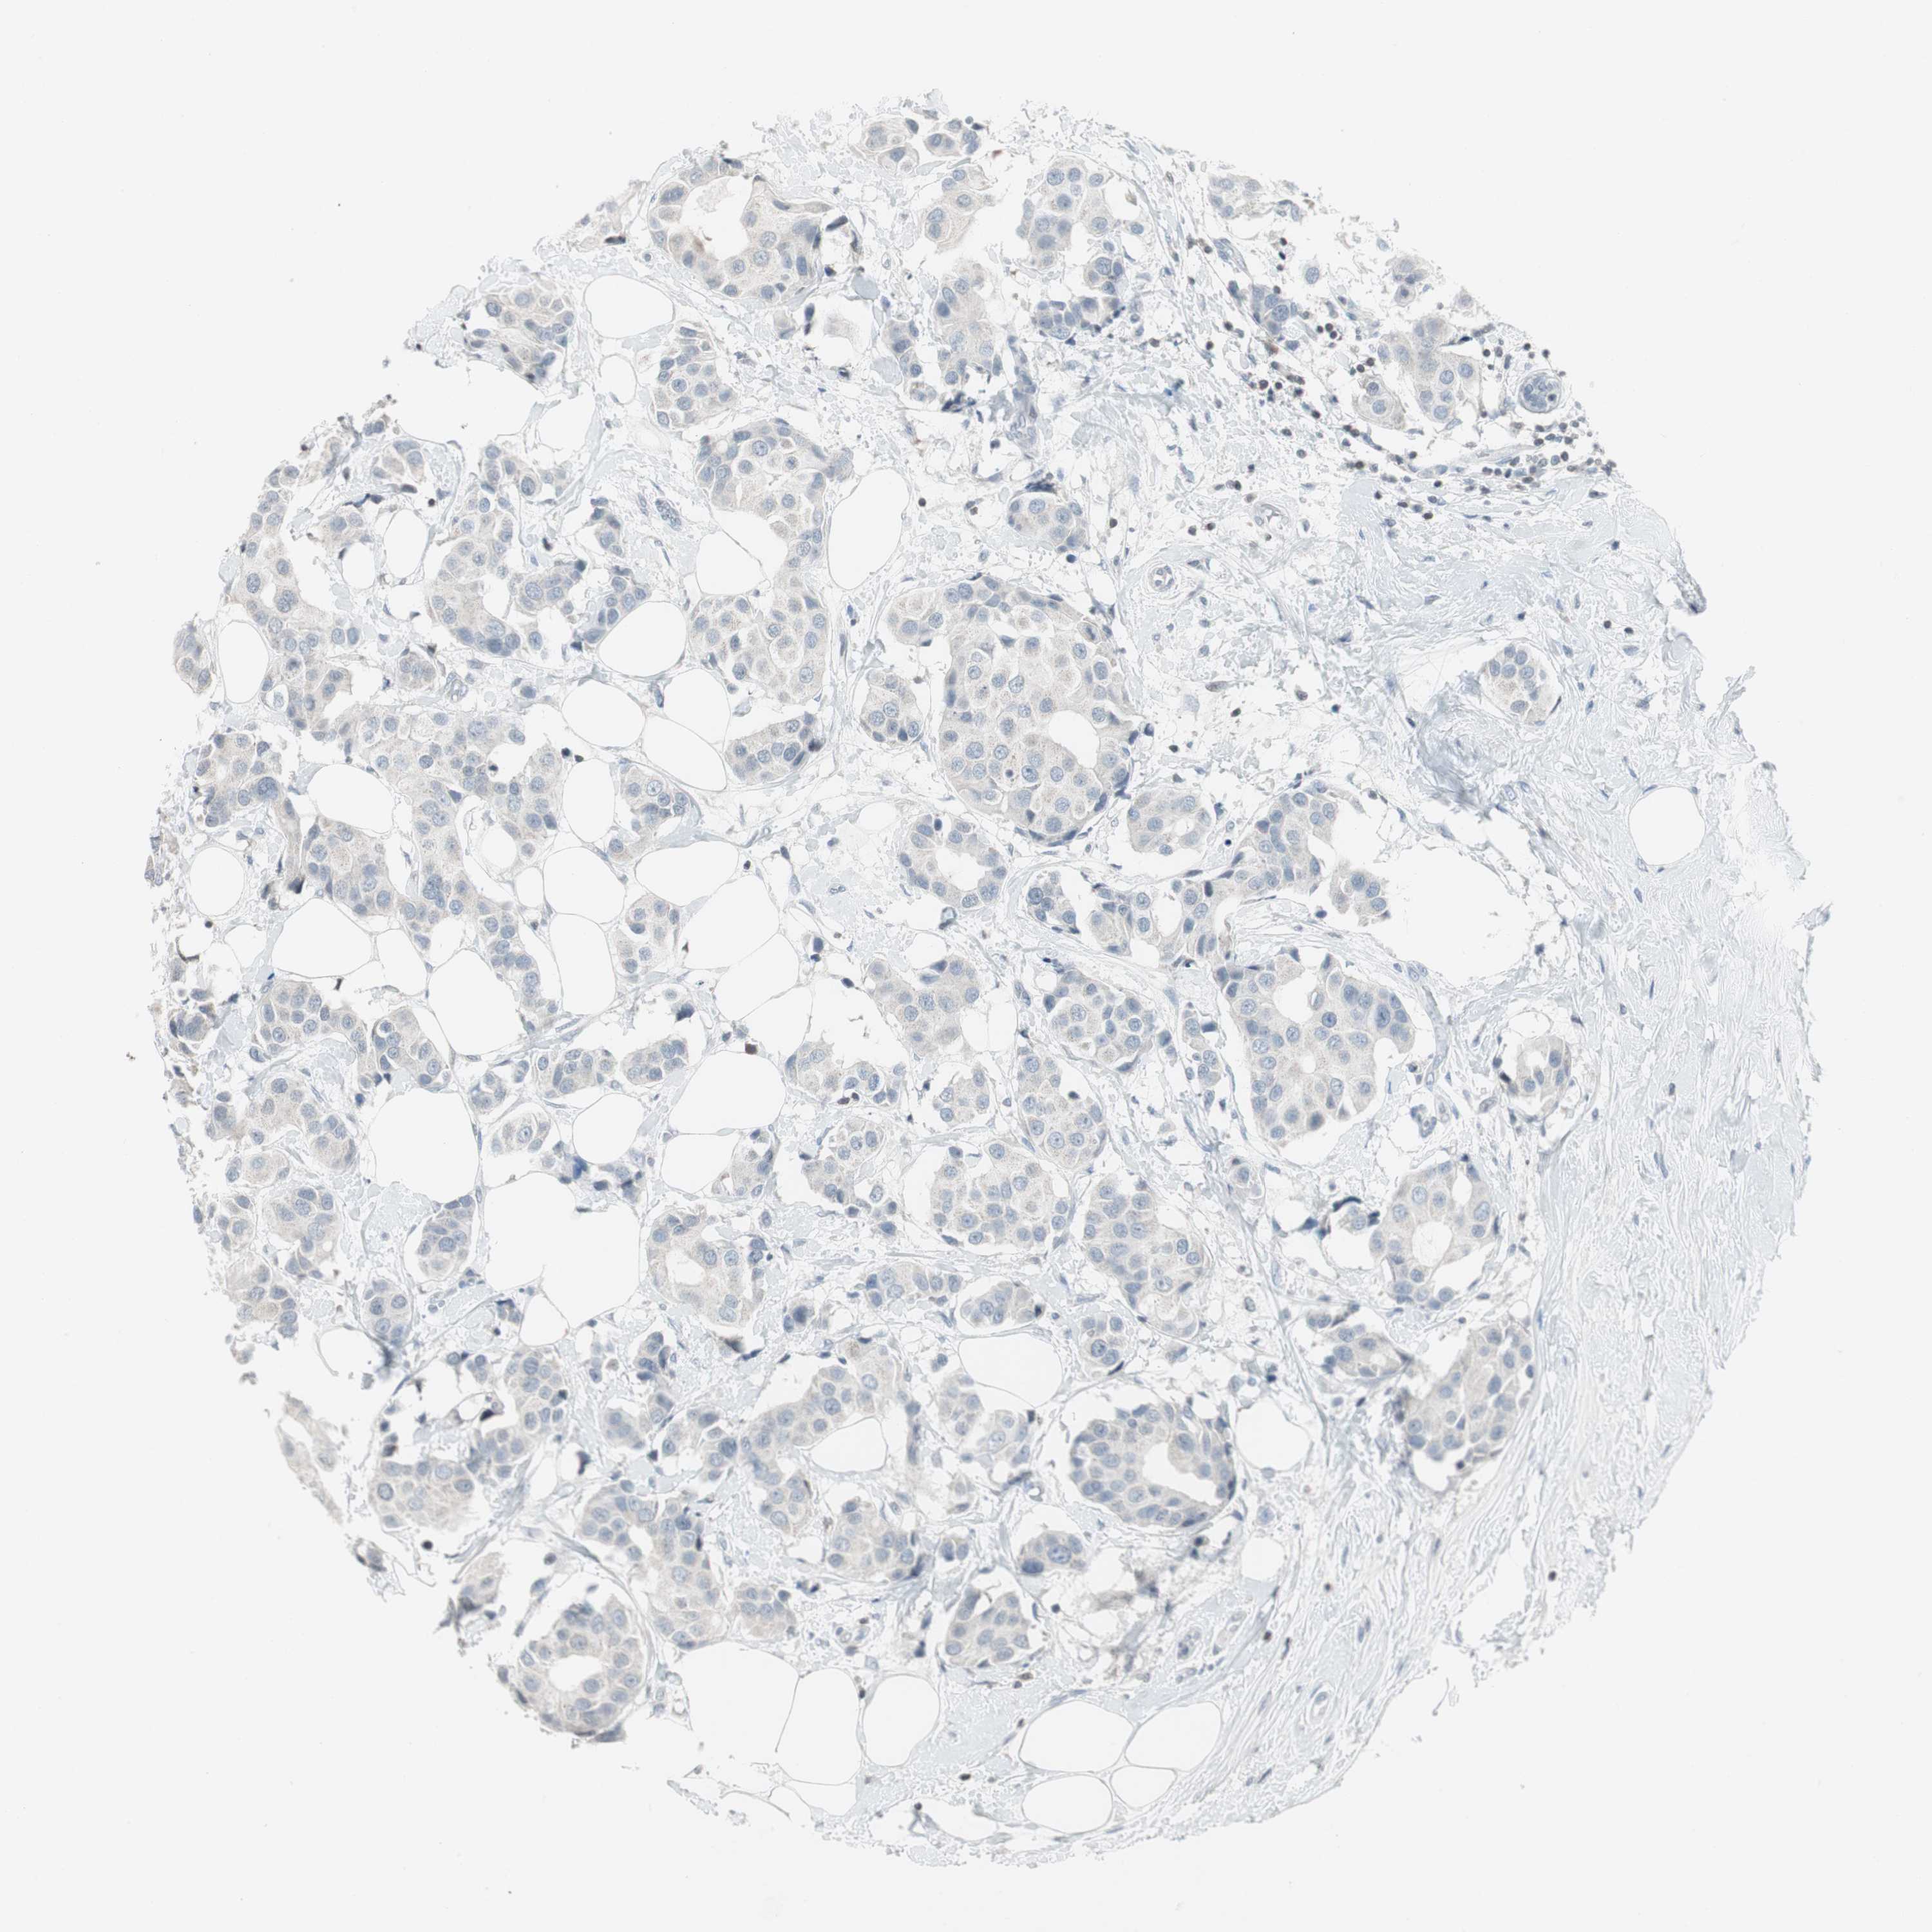

BRCA TCGA BRCA VALIDATION PROTEIN EXPRESSION

ANTIBODIES

AND

VALIDATION